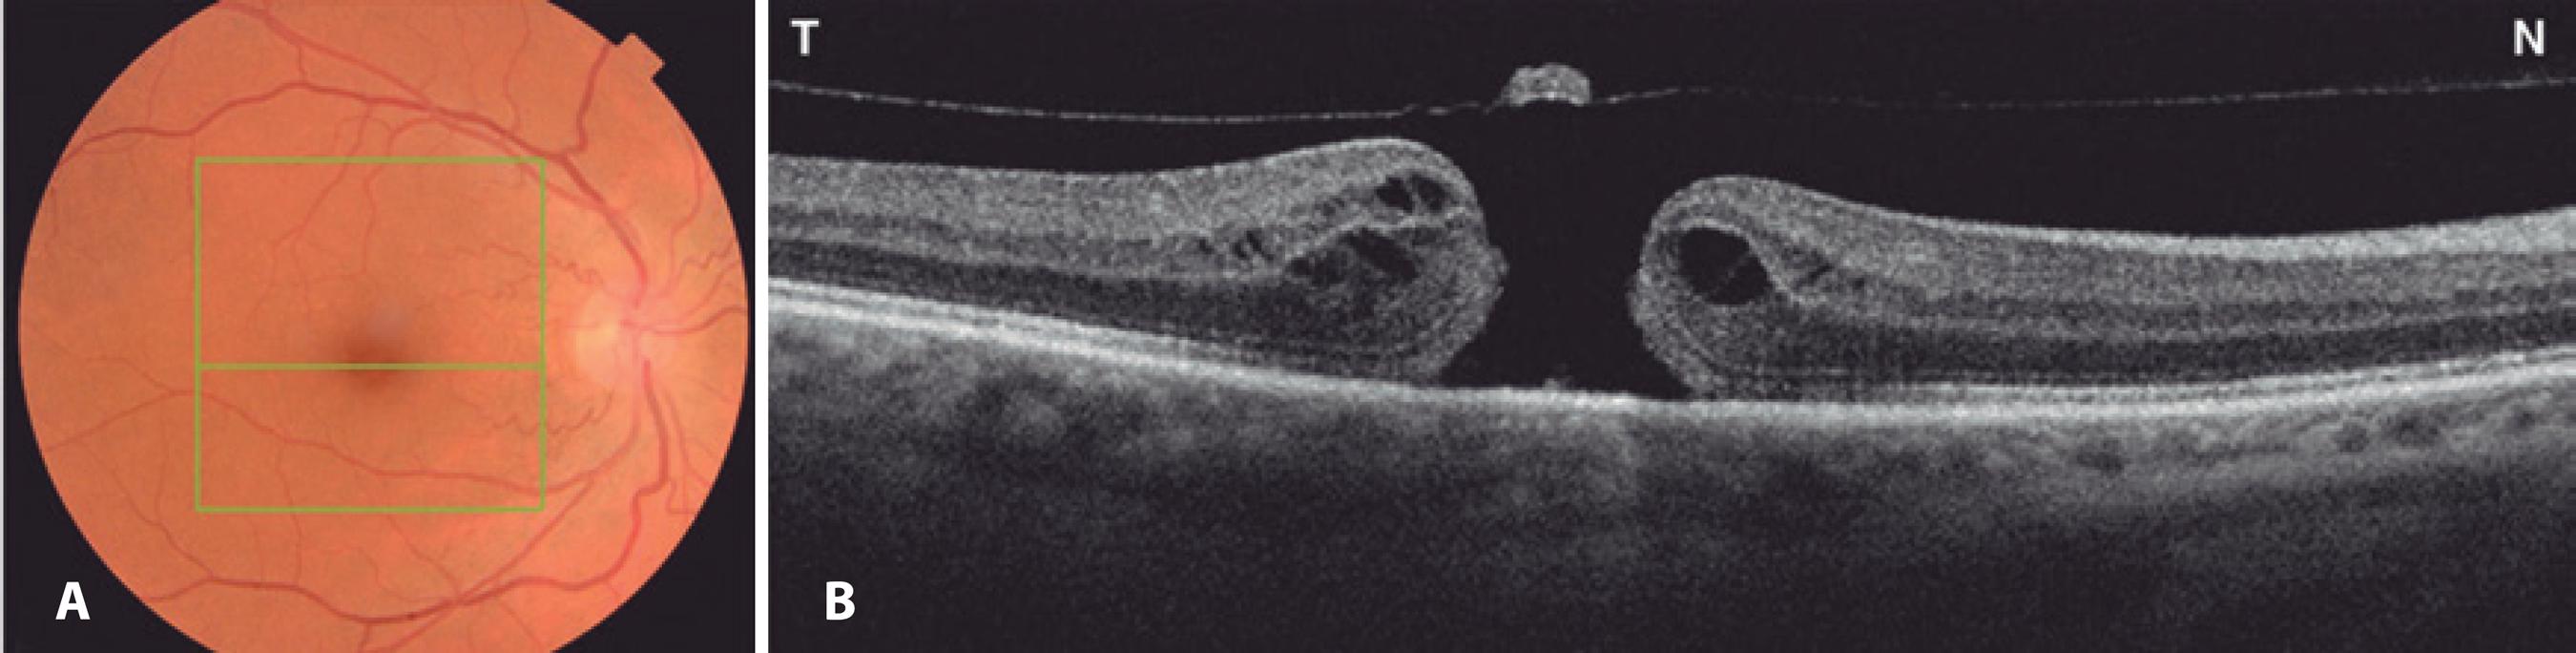

A 56-year-old previously healthy woman reported a 6-month history of progressive visual decline in her right eye (OD). Her past medical history was unremarkable, with no history of stroke, myocardial infarction, dyslipidemia, sleep apnea syndrome, or smoking. Best-corrected visual acuity (VA) was 20/200 in OD, 20/20 in the left eye (OS). Slit lamp examination was normal; the patient was phakic, and the anterior chamber angle was wide open in both eyes on gonioscopy. IOP was 18 mmHg in OD and 19 mmHg in OS. Fundus examination revealed normal optic nerves with a cup-to-disc ratio of 0.2, partial posterior vitreous detachment, and a macular hole in OD (Figure 1 A), and was normal in OS. Optical coherence tomography (OCT) showed a full-thickness macular hole with overlying operculum (Figure 1 B). Under retrobulbar anesthesia, she underwent an uneventful 25-gauge posterior PPV with posterior hyaloid separation followed by internal limiting membrane (ILM) staining with brilliant blue G (Ophthalmos™, Brazil) for 30 s. Subsequently, intraocular forceps were used to circumferentially peel ILM around the macular hole. A few self-limited, small, superficial, pre-retinal hemorrhages occurred in the peeled macular area. Then, fluid-air exchange and air-gas exchange with 20% SF6 were performed. No hyper- or hypotensive events were observed intraoperatively. The patient was instructed to maintain a face-down position for 5 days postoperatively.

Figure 1 A) Preoperative fundus retinography demonstrating normal optic nerves with a small cup-to-disc ratio and macular hole affecting the right eye. The green square represents the area of the macular hole (6 × 6 mm) on optical coherence tomography (OCT). The central green horizontal line represents the OCT scan through the center of the fovea. B) OCT (horizontal scan) of the same eye demonstrating a full-thickness macular hole with overlying operculum.